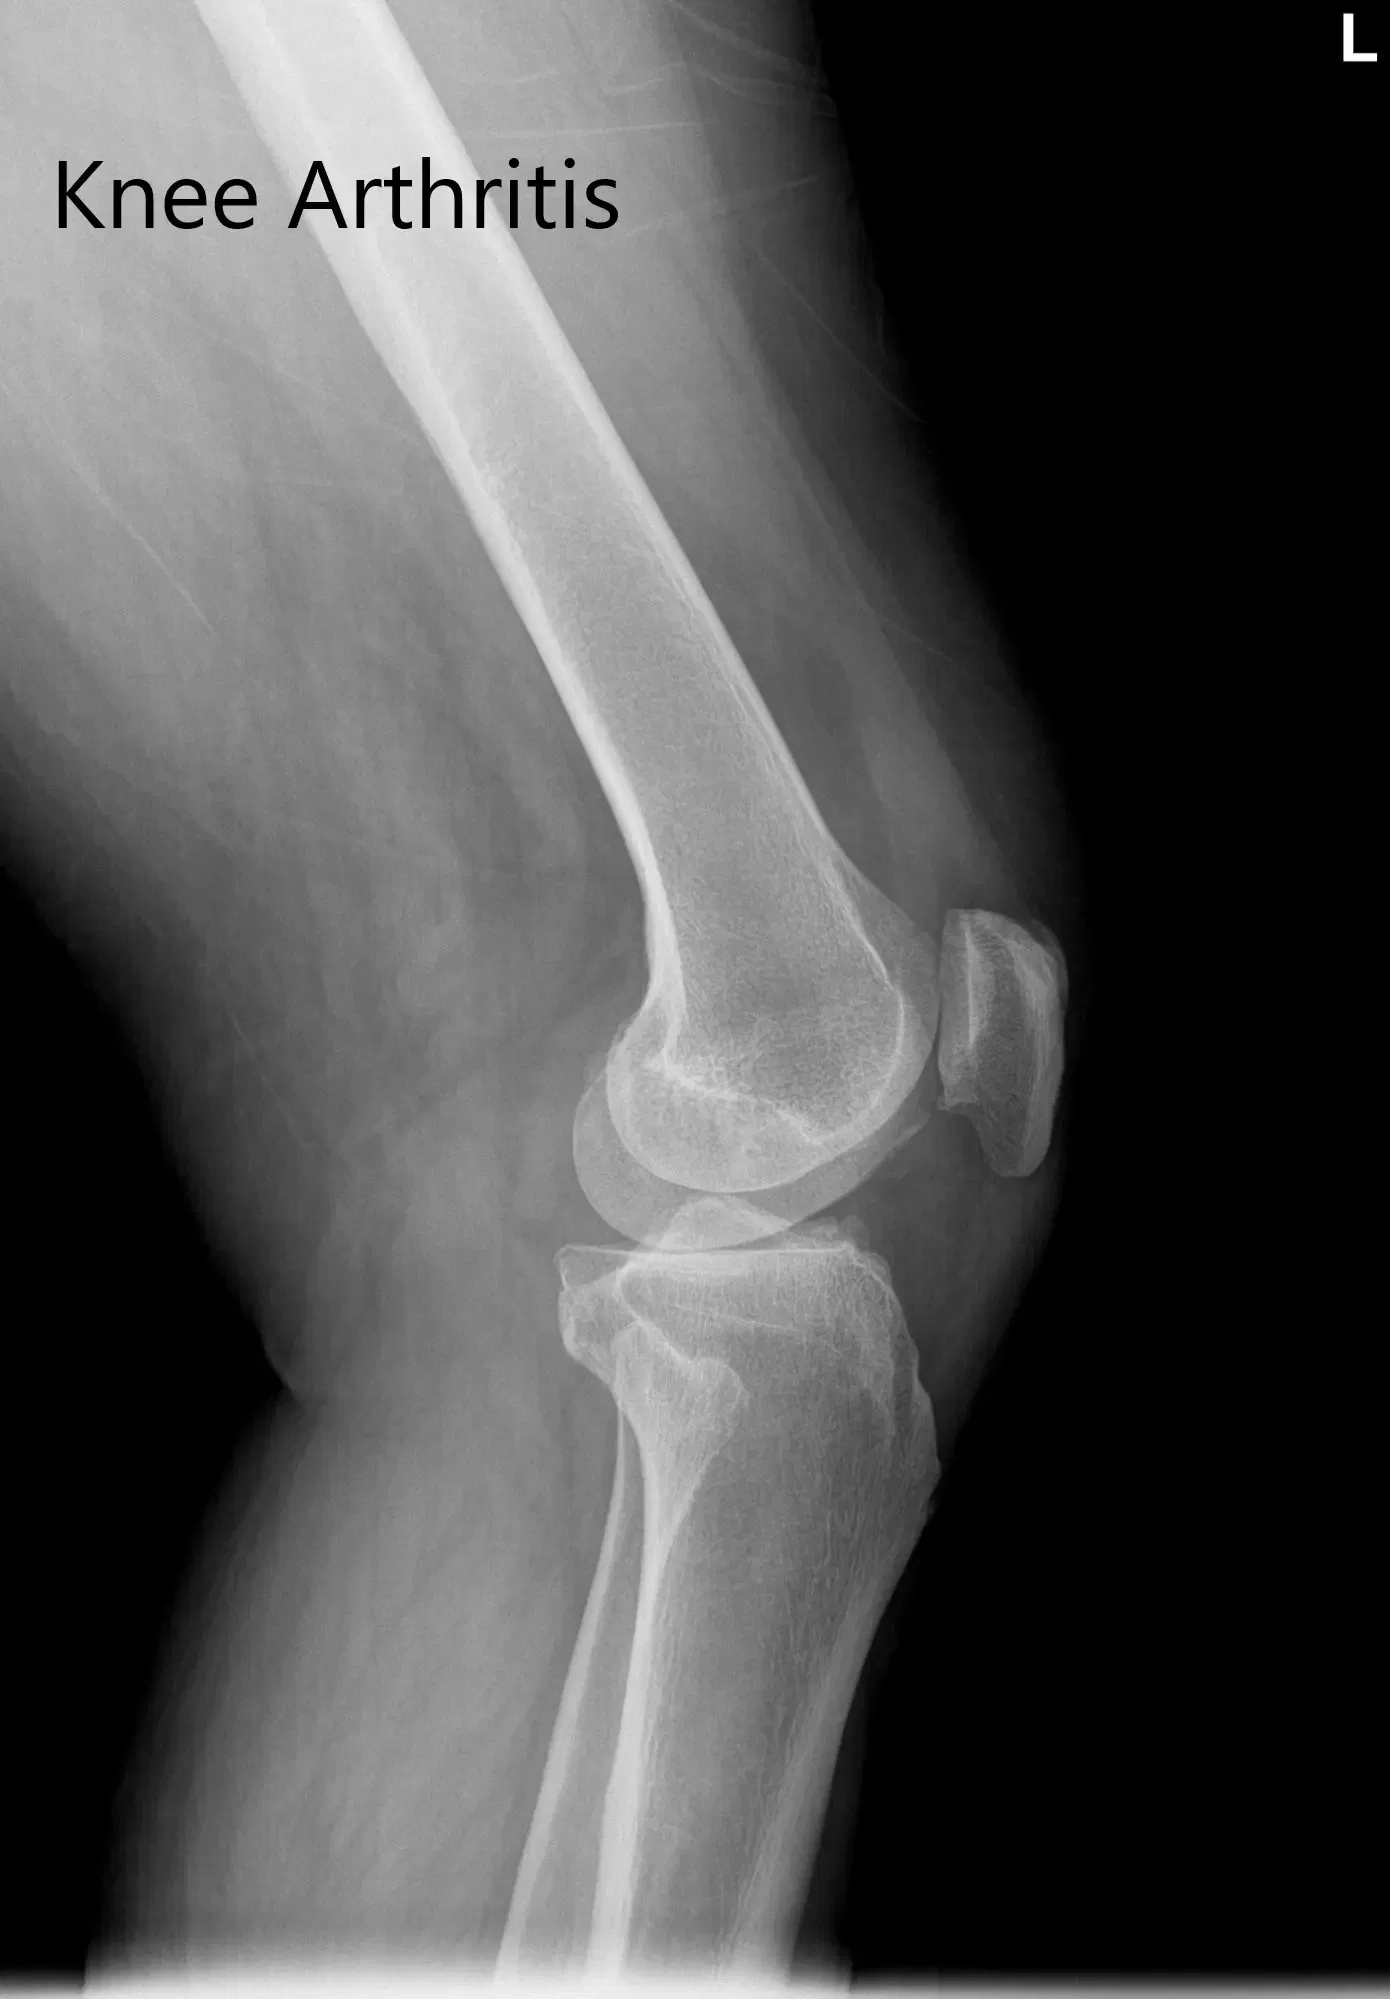

Radiografía preoperatoria de la rodilla izquierda que mostró visión AP y lateral

Los estudios de imagen demostraron el estrechamiento del espacio articular medial con cambios degenerativos. Se realizó una tomografía computarizada de la rodilla izquierda del paciente con cadera y tobillo unas semanas antes de la cirugía, demostrando osteoartritis tricompartimental. Los datos de la tomografía computarizada se utilizaron para crear un modelo 3D de la anatomía del paciente. Los datos se usaron después para crear implantes e instrumentos personalizados.